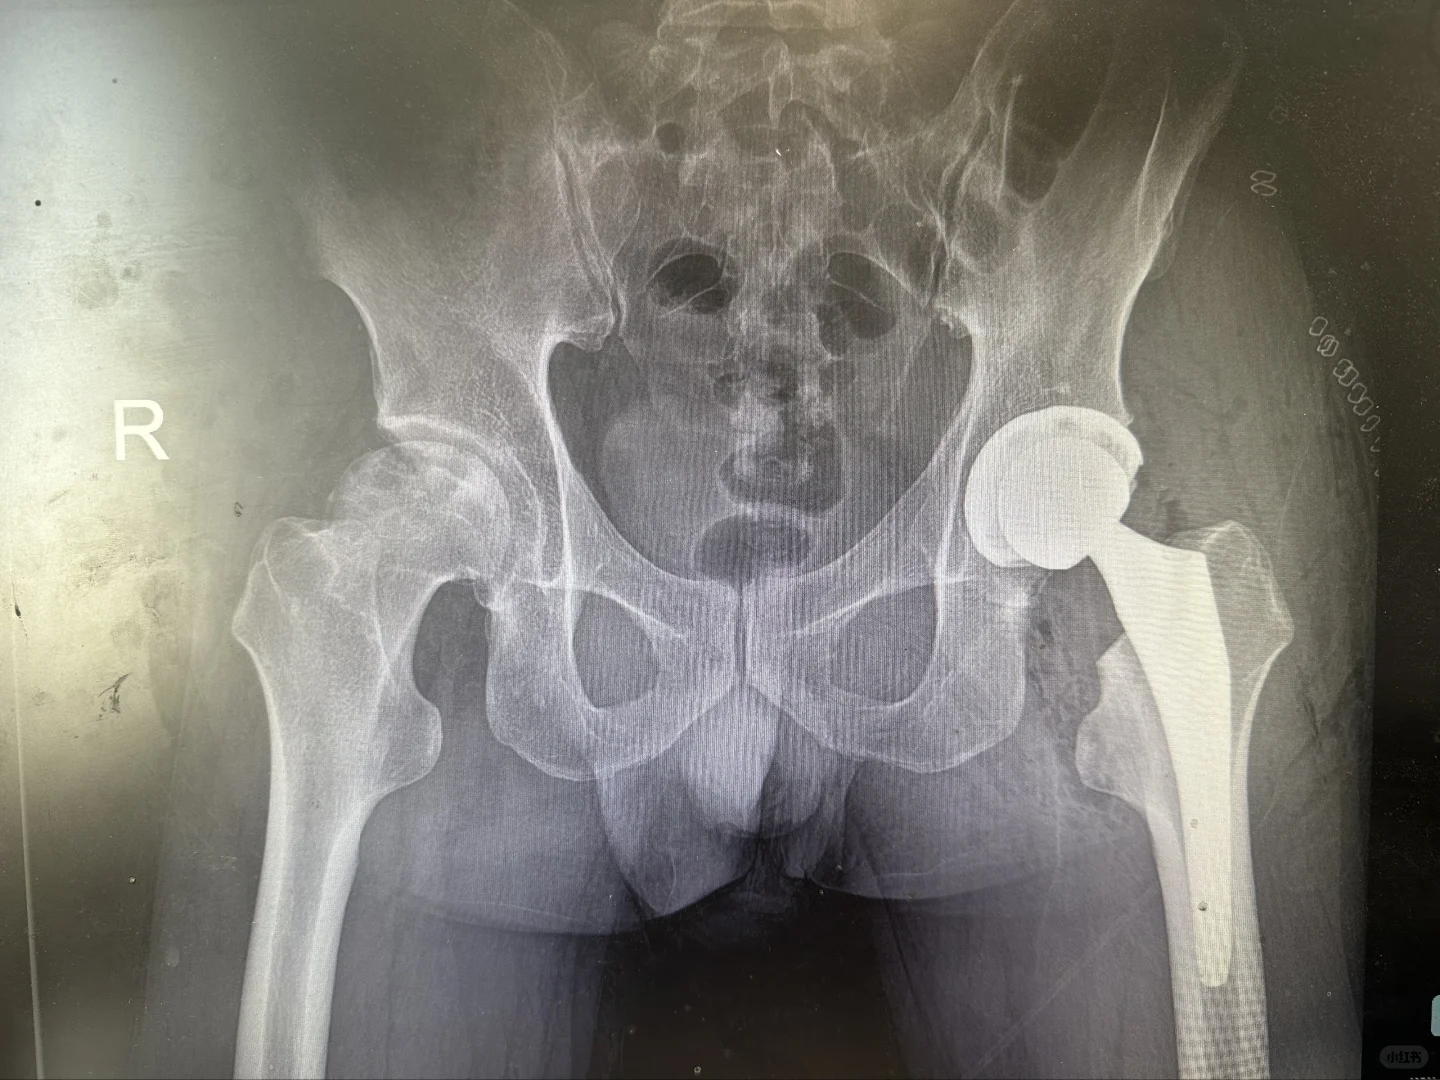

髋膝关节置换手术是二十世纪以来最成熟的手术,1小时的手术时间能够给患者带来关节的重生,从此告别让人无法忍受的疼痛,回归正常生活,老人上下楼梯爬山跳舞不是梦。

给大家看看我们的手术器械和术后影像,抡大锤的马医生在线回复您的疑问,点个关注,持续解答。